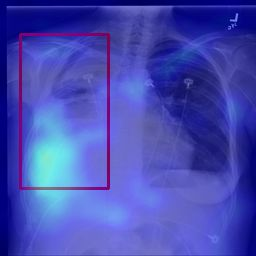

Deployments of artificial intelligence in medical diagnostics mandate not just accuracy and efficacy but also trust, emphasizing the need for explainability in machine decisions. The recent trend in automated medical image diagnostics leans towards the deployment of Transformer-based architectures, credited to their impressive capabilities. Since the self-attention feature of transformers contributes towards identifying crucial regions during the classification process, they enhance the trustability of the methods. However, the complex intricacies of these attention mechanisms may fall short of effectively pinpointing the regions of interest directly influencing AI decisions. Our research endeavors to innovate a unique attention block that underscores the correlation between 'regions' rather than 'pixels'. To address this challenge, we introduce an innovative system grounded in prototype learning, featuring an advanced self-attention mechanism that goes beyond conventional ad-hoc visual explanation techniques by offering comprehensible visual insights. A combined quantitative and qualitative methodological approach was used to demonstrate the effectiveness of the proposed method on the large-scale NIH chest X-ray dataset. Experimental results showed that our proposed method offers a promising direction for explainability, which can lead to the development of more trustable systems, which can facilitate easier and rapid adoption of such technology into routine clinics. The code is available at www.github.com/NUBagcilab/r2r_proto.